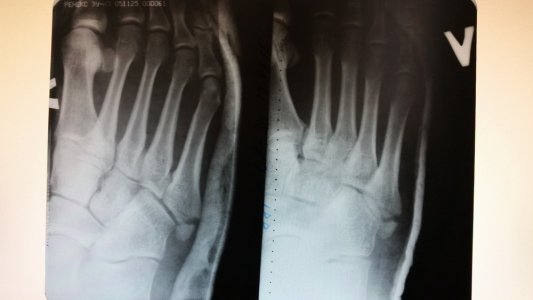

перелом 5 плюсневой кости

Извините, мне дали снимок на диске, только могу скрин экрана сделать, я хотела спросить насколько сложен перелом, сколько будет длится реабилитация, а также у меня гипс ломается можно ли снять через неделю (будет 3недели с гипсом), и использовать эластичный бинт? Спасибо вам большое!

Я не вижу перелом, плохая картинка. Скорее всего 4 недели достаточно, все в ваших руках, можно и 3...

Дбрый день, необходима консультация

поставили диагноз, закрытый перелом основания 5 плюсневой кости левой стопы со смещением.

Предлагают делать операцию, как думаете стоит ли, или можно обойтись и без нее.

Если возраст молодой, физическая активность высокая - лучше оперировать. Можно не оперировать, если не планируете футбол...